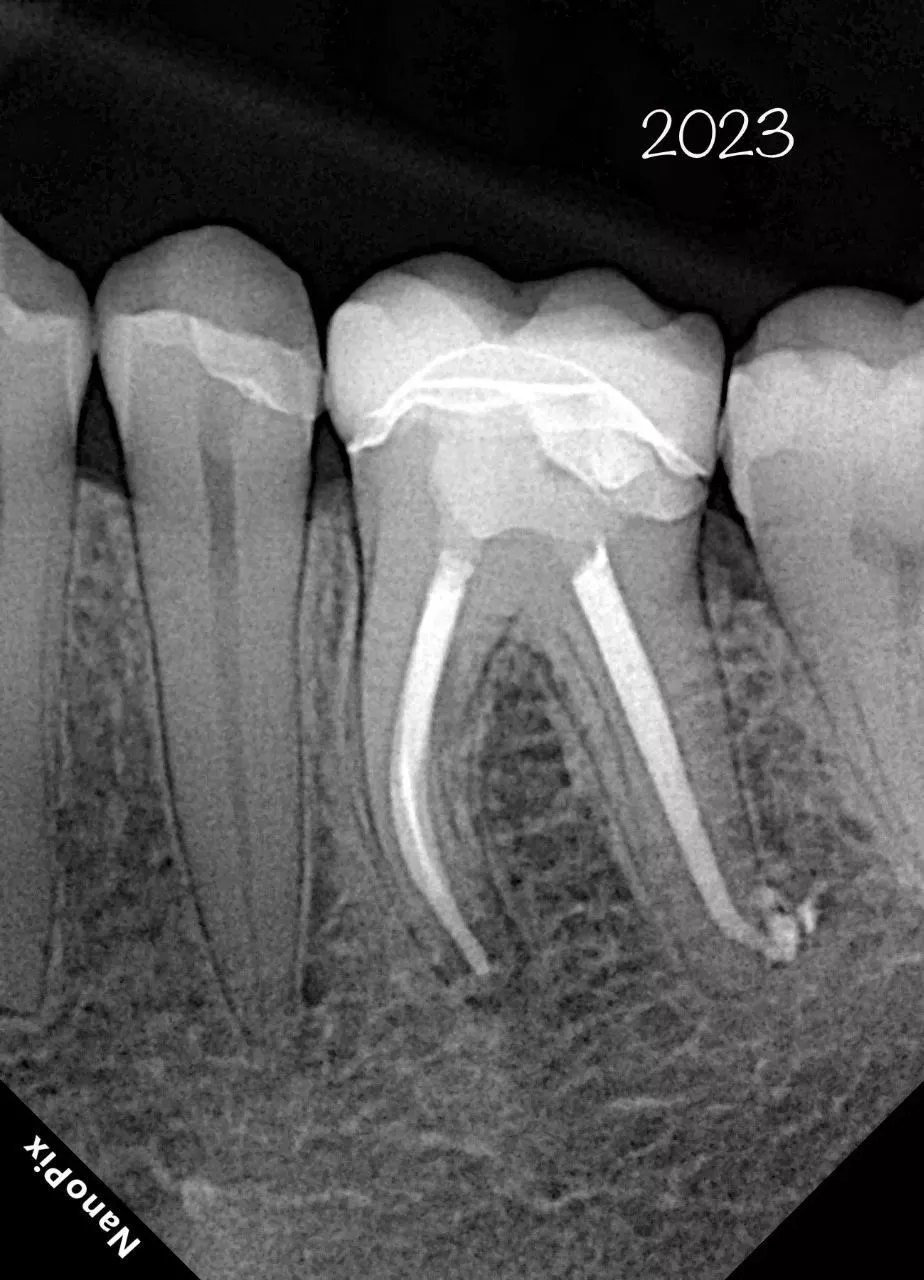

Прибор оснащён высокочувствительным сенсором, с помощью которого устройство фиксирует и передаёт изображение в цифровом виде на компьютер. Принцип работы заключается в следующем: цифровой радиовизиограф размещается в ротовой полости пациента за зубами. С щёчной стороны дентальный рентгеновский аппарат выпускает в направлении радиовизиографа рентгеновские лучи. Лучи, проходя через ткани зуба, фиксируются на радиовизиографе, и полученная информация отображается на экране компьютера. Уникальная технология искусственного интеллекта Nano AI распознаёт зубные патологии, выделяя их цветом и предлагая возможные способы лечения.

- Технология APS CMOS обеспечивает высокое соотношение сигнал/шум и позволяет получать четкие и чистые изображения с максимальной детализацией;

- Технология прямого осаждения CsI позволяет сделать снимок при минимальной безопасной дозе рентгеновского облучения;